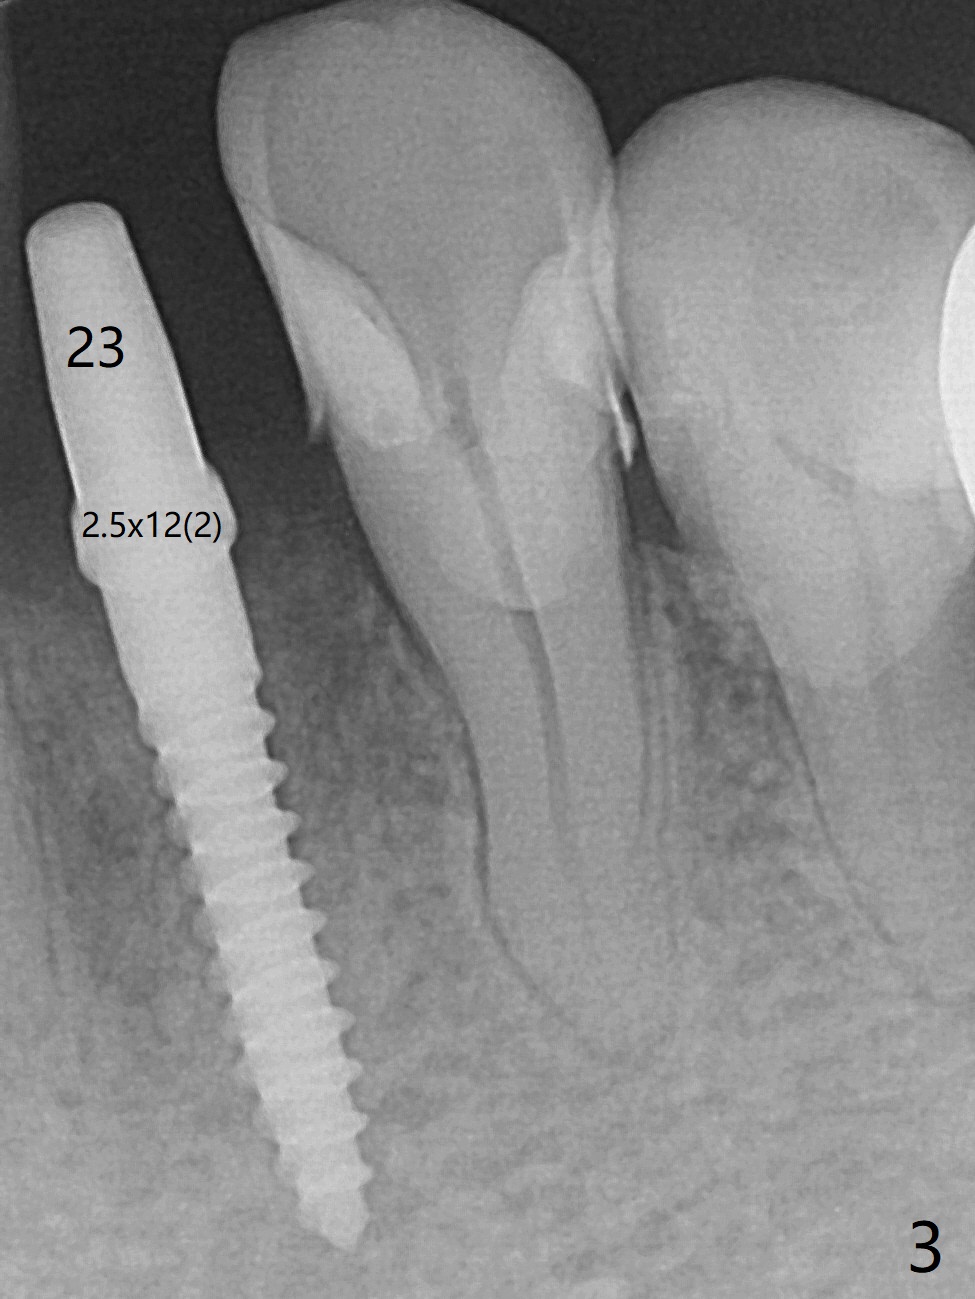

术前检查植牙位点角化龈,好像不太成熟(23,29号牙位点保存2个月,26号牙4个月),所以切开。翻瓣后,放置导板,29号牙位有意减少钻洞直径,用完3毫米钻头后,颊侧骨板已经薄,因此放入3.8x8.5毫米植体(设计4.5x8.5),颊侧植体顶端略微暴露,种深0.5毫米,之后颊侧放置自体骨和异体骨(图一:*)。26号牙钻洞也偏颊侧,所以选择4毫米袖的一段式植体,可以种深(图二,与图三对比),植入自体骨后,使用胎盘膜覆盖。由于没有特别一段式植体导板钻头,最细钻头2.2毫米,所以扭力低,没有即刻修复,下次应该减少钻洞深度,增加扭力。